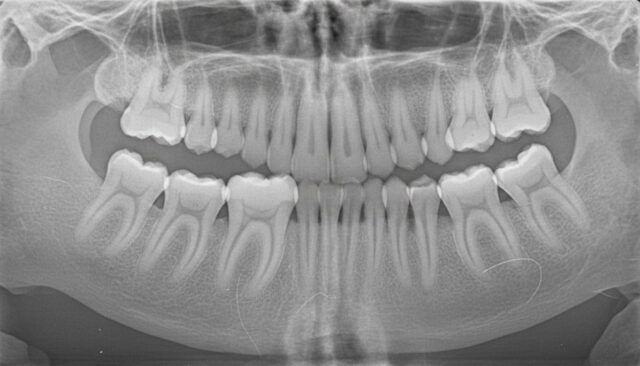

レントゲン検査の重要性

目視だけでは確認できない親知らずの状態を把握するため、定期的なレントゲン検査が重要です。

レントゲン検査により、親知らずの位置の変化、むし歯の有無、周囲の骨の状態などを確認できます。特に完全に埋まっている親知らずの場合、レントゲン検査なしでは状態を把握することができません。

骨の中に完全に埋まっていて、レントゲン写真上で問題が認められない場合も抜歯の必要はありません。

他の歯に影響を及ぼさなければ経過観察を続けることができます。ただし、定期的なレントゲン検査で状態を確認することが重要です。